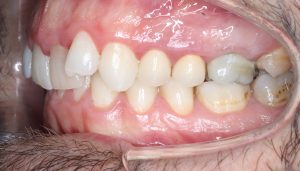

Maloclusión Clase III

La maloclusión dental de clase III se presenta cuando los dientes inferiores están más adelantados que los superiores, lo que provoca una sobremordida invertida.

Esta condición puede generar problemas en la mordida, dificultad para masticar y afectar la estética facial, especialmente en la proyección de la mandíbula.

FULL

37 Semanas de tratamiento